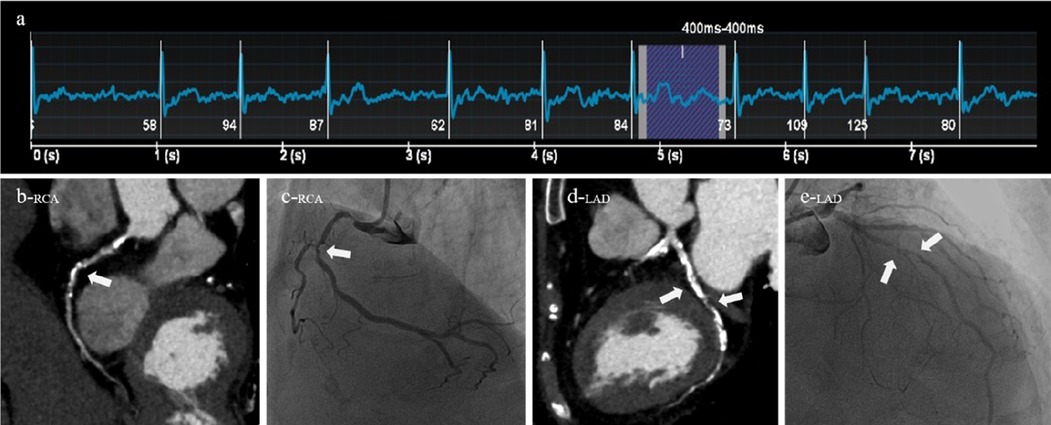

Figure 5

A 84-year-old male patient was clinically diagnosed with atrial fibrillation and arrhythmia. Both CT (AI-ADS, AI-ADS + radiologist) and ICA showed severe stenoses of the first segment of right coronary artery and the sixth and seventh segments of left anterior descending coronary artery, (a) ECG showed a heart rate of 84 beats/min and heart rate variability of 26 beats/min during the scan, (b) right coronary artery, CPR, (c) right coronary artery, ICA, (d) left anterior descending coronary artery, CPR, (e) left anterior descending coronary artery, ICA.